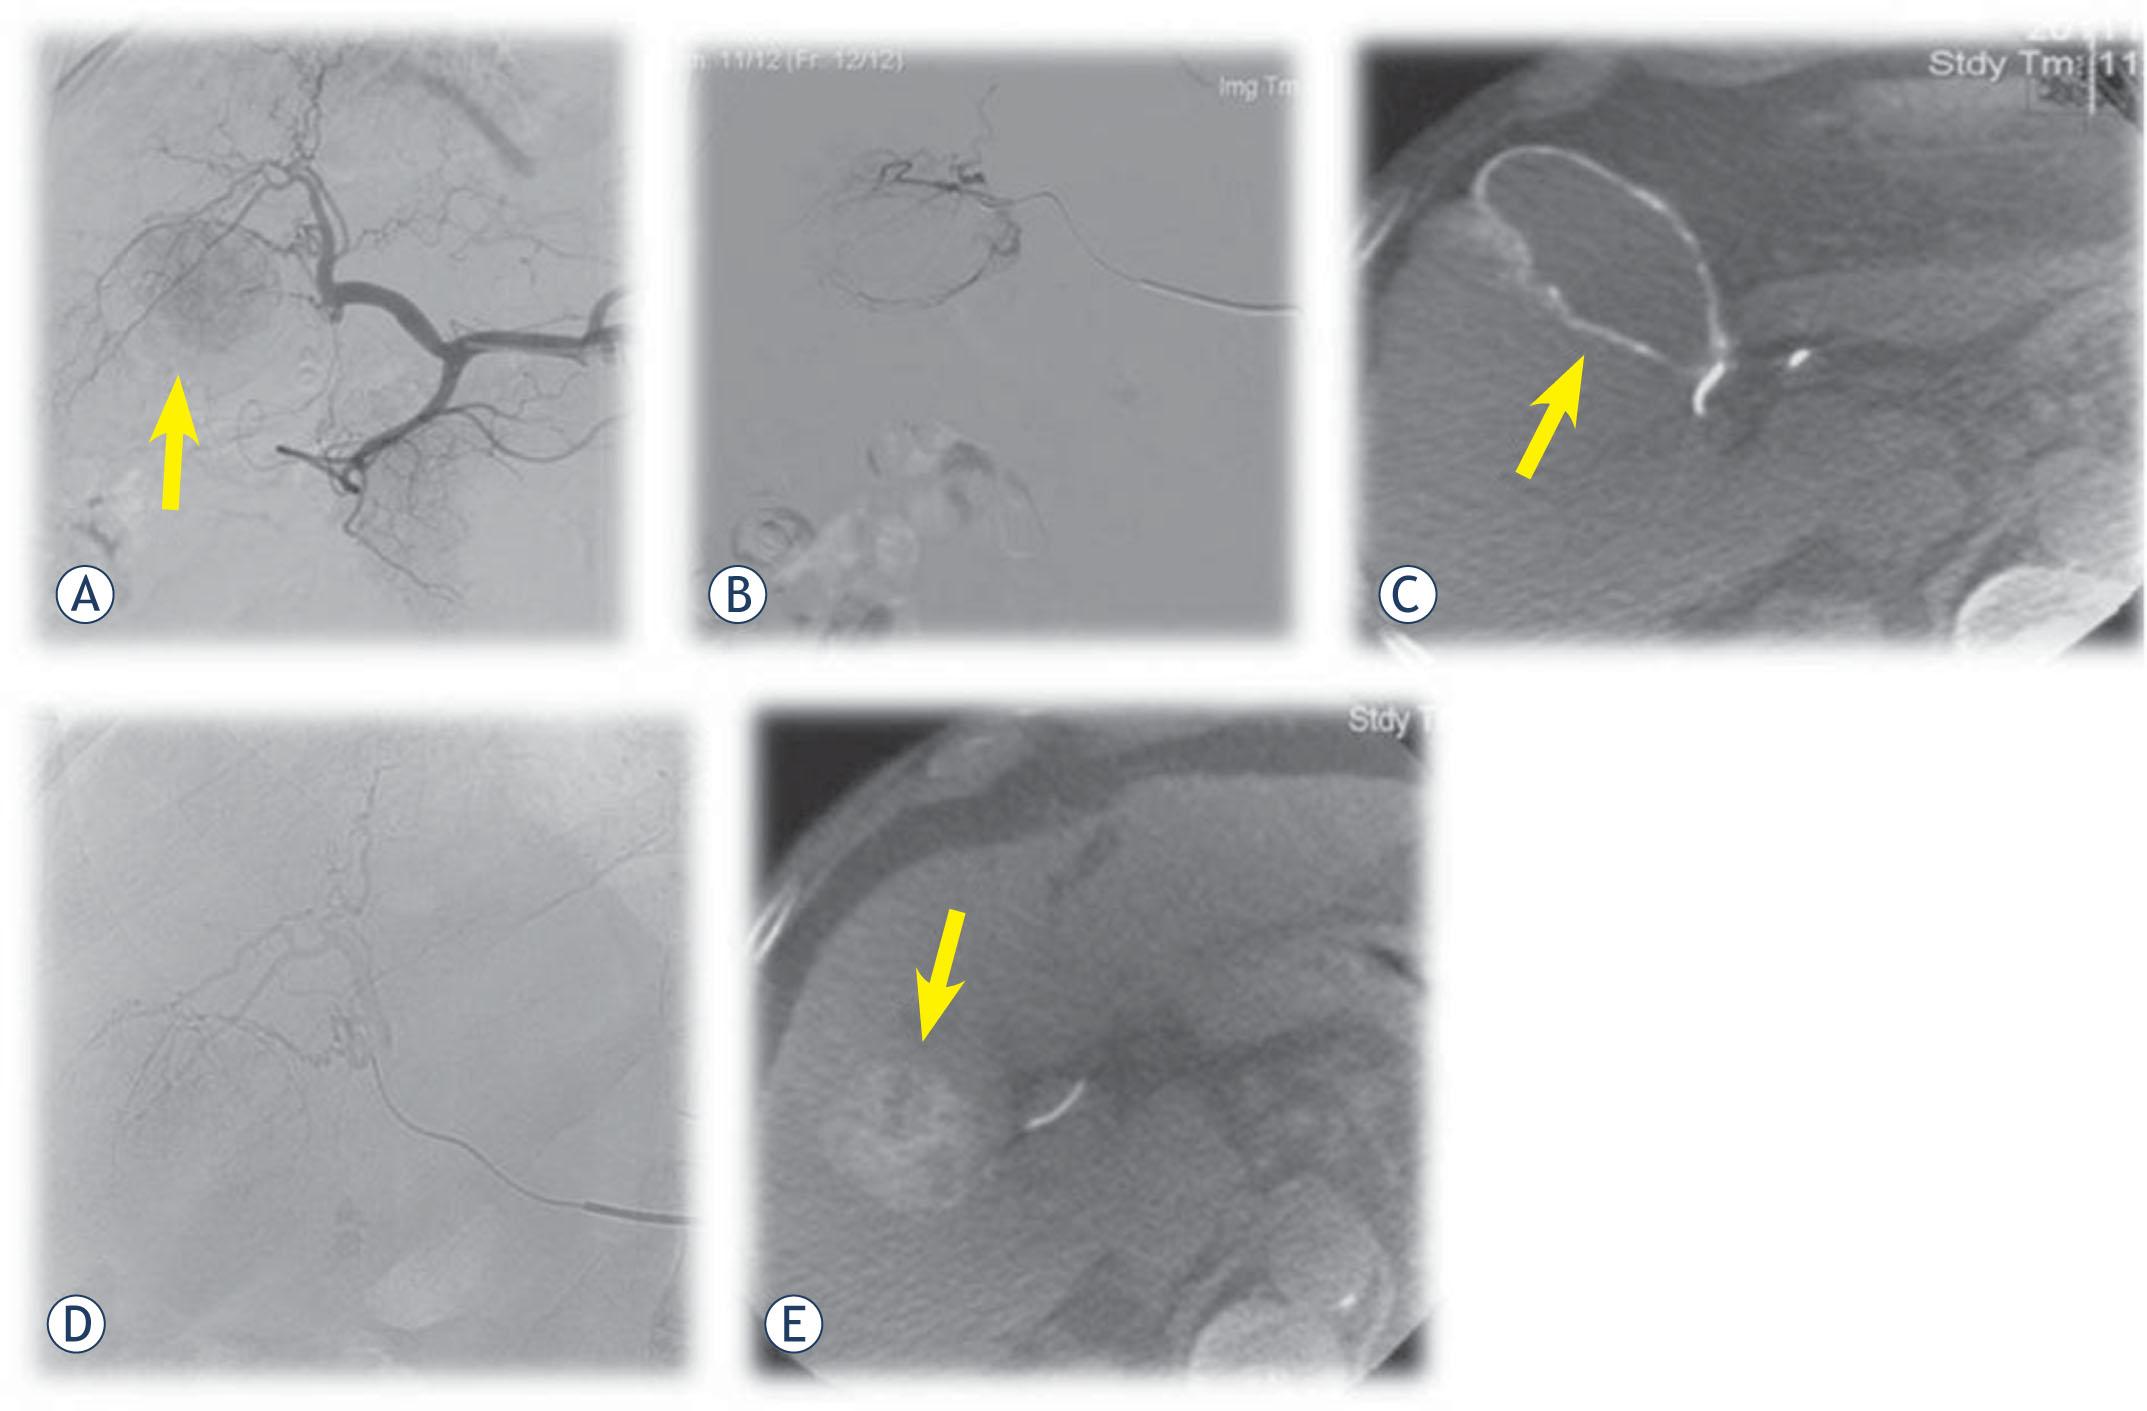

All patients underwent C-arm single phase CBCT. Imaging was performed by using a commercially available angiography system (Allura Xper FD20®; Philips HealthCare). This system was equipped with the XperCT option, enabling C-arm CBCT acquisition and volumetric image reconstruction (Feldkamp back projection). For each CBCT scan, the area of interest was positioned in the system isocenter, and, over approximately 10 seconds, 310 projection images were acquired with the motorized C-arm, covering a 240° clockwise arc at a rotation speed of 20° per second. As the images were being acquired, the projections were transferred via fiber-optic connection to the workstation (Philips Xtravision, Rel 6.2; Dell Precision 670; Round Rock, TX/USA). The two-dimensional projection images were reconstructed by using Feldkamp back projection into three-dimensional volumetric images with isotropic resolution of 0.98 mm for a 250 × 250 × 194-mm field of view (matrix size, 256 × 256 × 198). Typically, a 2.4-French microcatheter (Progreat®, Terumo Europe N.V.) was advanced into either a subsegmental or a segmental hepatic artery, depending on the location of the targeted tumor. CBCT was performed with the administration of non-ionic contrast agent (Ultravist 370®, Bayer HealthCare) through a power injector (Avanta®, Medrad, Bayer HealthCare). The injection rate was typically 1mL/s with a total injected volume of contrast agent 10 mL and delay time 15 seconds. The patients were instructed to be at endexpiration apnea during each CBCT acquisition. The final position of the microcatheter for delivery of the DEBs was based on the results of C-arm CBCT. This was done to superselectively deliver the bead to the tumors (Figure 3).

A 66-year-old male with HCC. (A) Initial angiography shows tumor in right liver lobe (arrow). (B) Superselective contrast injection throught microcatheter into the subsegmental branches. (C) CBCT shows that this artery actually suplied the gallblader (arrow) and not the target tumor. (D) Superselective catheterisation of the tumor feeding artery with microcathter. (E) CBCT after contrast injection throught microcatheter confirmes the target lesion (arrow). Superselective DEBDOX TACE was performed.